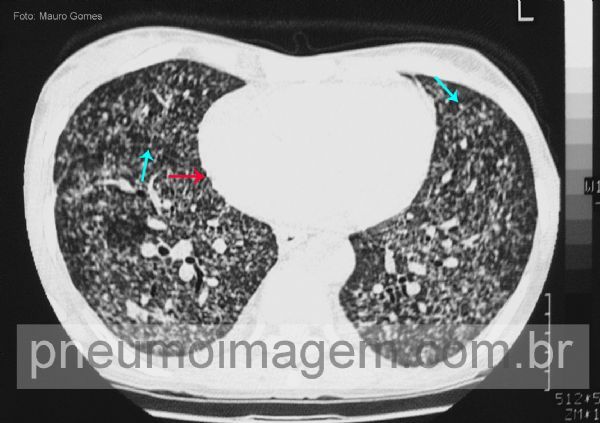

Nas metástases do carcinoma de tireóide os nódulos são pequenos e com distribuição aleatória em relação às estruturas do lóbulo secundário. Neste corte ainda se observam nódulos subpleurais (setas azuis) e ao longo do feixe peribroncovascular (setas vermelhas) dando um aspecto nodular nas ramificações da artéria pulmonar. Há também espessamento dos septos interlobulares (seta amarela), possivelmente relacionado à linfangite carcinomatosa.

In thyroid malignancy metastases, the nodules are small and randomized in relation to the secondary lobule structures. In this CT slice, subpleural nodules are observed (blue arrows) and peribronchovascular (red arrows) giving a nodular feature on the branches of the pulmonary artery. There is also interlobular septal thickening (yellow arrow), possibly related to carcinomatous lymphangitis.